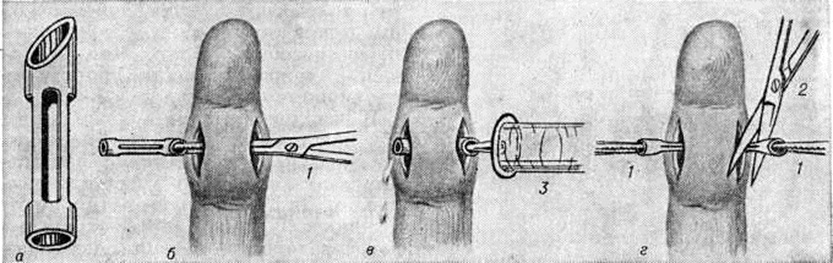

Лечение подногтевого Панариций только оперативное. При расположении гноя вблизи свободного края тела ногтя ногтевую пластинку иссекают под местной анестезией в виде клина. Часто в таких случаях обнаруживается инородное тело — заноза, явившаяся причиной Панариций Полностью удаляют ноготь (рисунок 10) только при отслойке его гноем на большом протяжении.